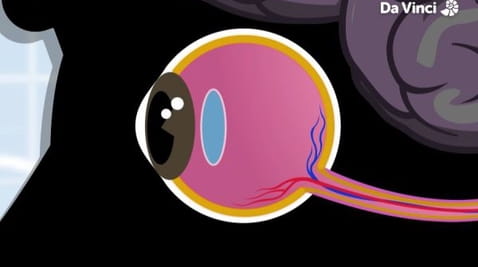

6. Kątem oka

3. Od środka historia oczu i tłuszczu